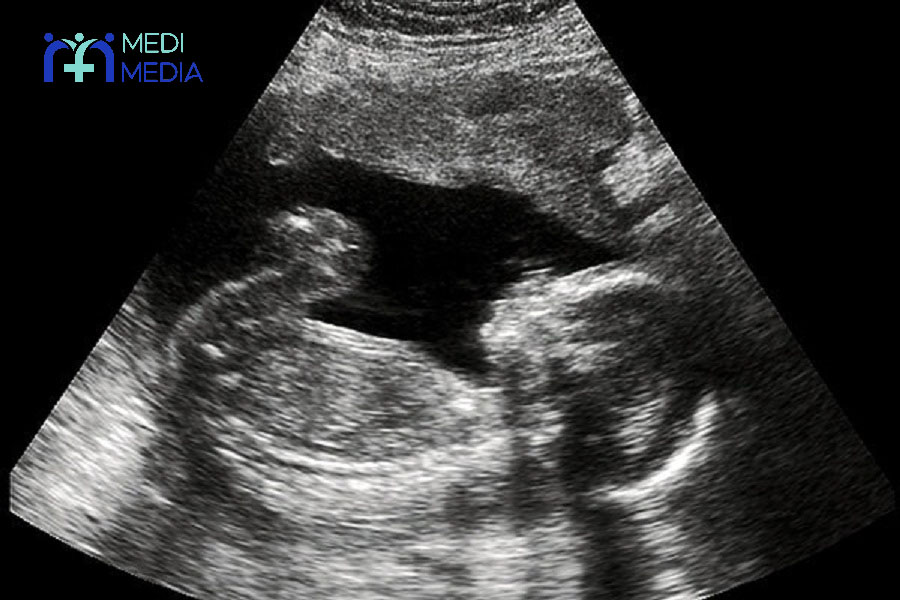

ارزیابی جنین

در یک خانم حامله مبتلا به آسم، نوع ارزیابی جنین و دفعات آن بر اساس سن حاملگی و عوامل خطر مادر تعیین می گردد. سونوگرافی قبل از هفته ی ۱۲ حاملگی در صورت وجود شبهه ای در مورد زمان حاملگی و بعد از آن در صورت کاهش رشد جنین باید انجام شود.

البته ارزیابی ضربان قلب جنین به روش های مرسوم در پزشکی نیز می تواند عامل مهمی برای ارزیابی سلامتی جنین باشد. در سه ماهه ی سوم بارداری در خانم های باردار با علائم شدید آسم، دفعات ارزیابی جنین باید افزایش یابد. ضمناً بیماران آسمی باید توجه بیشتری به تعداد حرکات جنین خود داشته باشند.

در طی یک حمله ی شدید آسم که علائم رو به بهبودی نیست، همان طور که پیش تر نیز گفتیم خطر پایین آمدن اکسیژن خون مادر وجود دارد، که در این حالت ارزیابی وضعیت جنین به خصوص از نظر میزان ضربان قلب حائز اهمیت است.